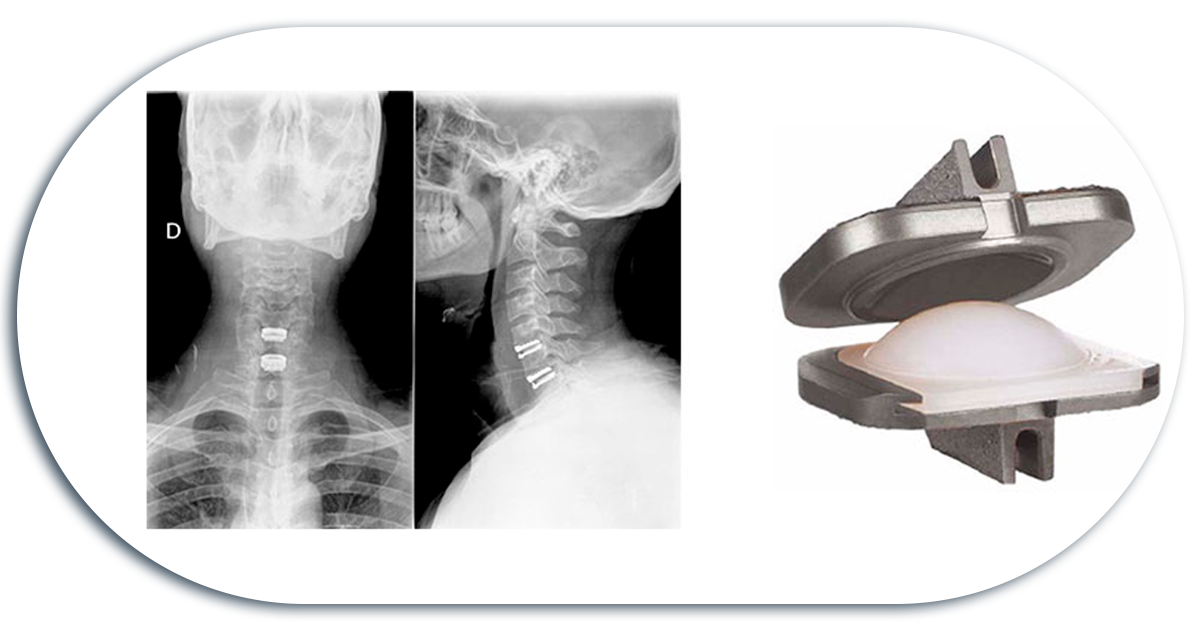

Placa Cervical

Se trata de un soporte laminar que se coloca en la parte anterior de la columna cervical tras una discoidectomía y/o colocación de cajas intersomaticas.

Sirve para darle mayor soporte a una columna cervical inestable pero sobre todo para evitar la migración y expulsión de los injertos de hueso que se colocaban entre los cuerpos vertebrales tras la resección del disco intervertebral.

Artroplastia / Prótesis De Disco

Para la preservacion del movimiento, se utilizan protesis de disco. Permiten la movilidad de la zona tratada en todos los ejes como son flexión, extensión, rotación y lateralización.

*No todos los pacientes son candidatos a recibir una protesis de disco, puesto que deben observarse todas las características de la zona afectada.